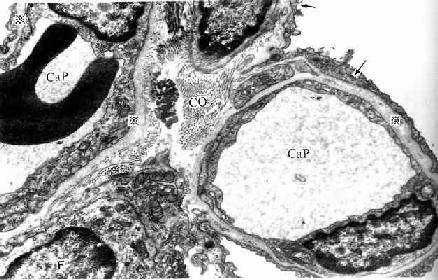

人肺泡隔电镜像

图14-15 人肺泡隔电镜像 ×13500

Cap毛细血管,F成纤维细胞,

CO胶原原纤维,※基膜,↑Ⅰ型肺泡细胞

(上海医科大学电镜室供图)

(2)肺泡隔( alveolar septum):相邻肺泡之间的薄层结缔组织构成肺泡隔,属肺的间质。肺泡隔内含密集的毛细血管网,毛细血管为连续型,内皮甚薄,无孔,胞质内含较多吞饮小泡。隔的厚薄不一,弹性纤维较丰富,也有少量胶原纤维网状纤维,并有成纤维细胞巨噬细胞浆细胞肥大细胞等以及淋巴管神经纤维。隔内丰富的弹性纤维有助于保持肺泡的弹性,老年人弹性纤维退化炎症等病变也可破坏弹性纤维,使肺泡弹性减弱,肺泡渐扩大,导致肺气肿,肺换气功能减低。隔内的毛细血管大多紧贴肺泡上皮,上皮基膜与内皮基膜相互融合;有的部位的肺泡上皮与毛细管内有少量结缔组织(图14-15)。

(4)气血屏障(blood-air barrier):肺泡内气体与血液内气体分子交换所通过的结构称气血屏障。它由以下结构组成:肺泡表面液体层、Ⅰ型肺泡细胞与基膜、薄层结缔组织、毛细血管基膜与内皮。有的部位的肺泡上皮与血管内皮之间无结缔组织,两层基膜直接相贴而融合(图14-15)。气血屏障很薄,总厚度约0.5μm。间质性肺炎时,肺泡隔结缔组织水肿,炎症细胞浸润,以致肺气体交换功能障碍